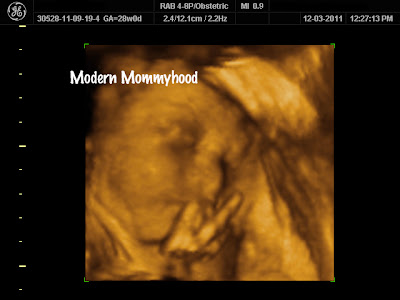

| Can’t tell which finger this is exactly…hoping she wasn’t mad at us for waking her up just for the ultrasound! |